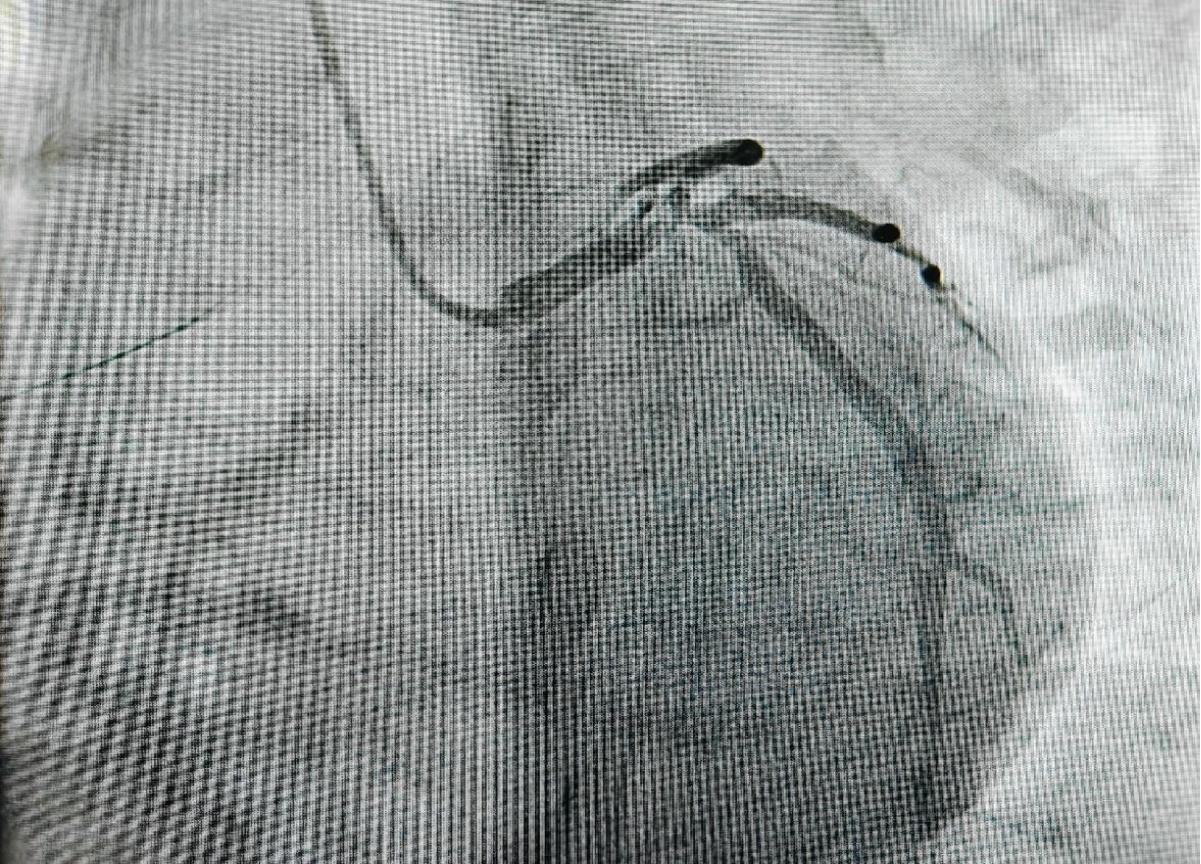

患者最初因胸痛前往当地医院就诊,当地医院通过冠脉造影检查发现,患者左主干末端呈现真性四分叉病变,且多支血管存在严重狭窄的情况,病情十分危急。鉴于患者病情的复杂性,当地医院联系了樱花动漫 ,随后患者转入院内进一步治疗。心血管内科楚天舒团队接诊后,立即启动应急响应机制,从决定为患者实施ECMO上机,到成功建立循环支持,仅耗时28分钟,为抢救患者赢得了宝贵时间。本次手术中,手术团队创造性运用主动脉内球囊反搏(IABP)+体外膜肺氧合(ECMO)双循环支持系统(IABP + ECMO), ECMO能够有效确保患者的血液循环稳定, IABP可以减轻心脏负担,改善心肌供血,两者协同配合,大大降低术中心脏骤停的风险,极大地提高了手术的安全性。

手术实施双主刀制度,由心血管内科介入团队与MICU紧密合作,确保循环支持与血运重建同步进行,全方位保障手术的顺利开展。术后,采用目标导向镇静策略,精准管理确保患者在48小时内成功撤除ECMO,有效降低了患者术后并发症。